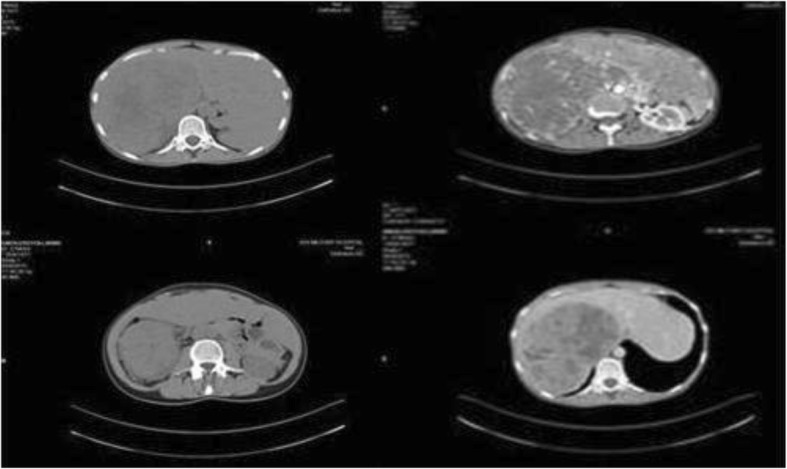

A computed tomography (CT) scan showed a large mass measuring approximately 24 cm in its greatest dimension (23.7 cm × 16.5 cm × 11.5 cm) that originated from her right adrenal gland and occupied her right abdomen, while compressing her right hepatic lobe and her inferior vena cava, and it was in contact with the right perirenal fascia of Gerota (Figs. 1 and 2).

Fig. 1.

Computed tomography appearance of giant adrenocortical carcinoma